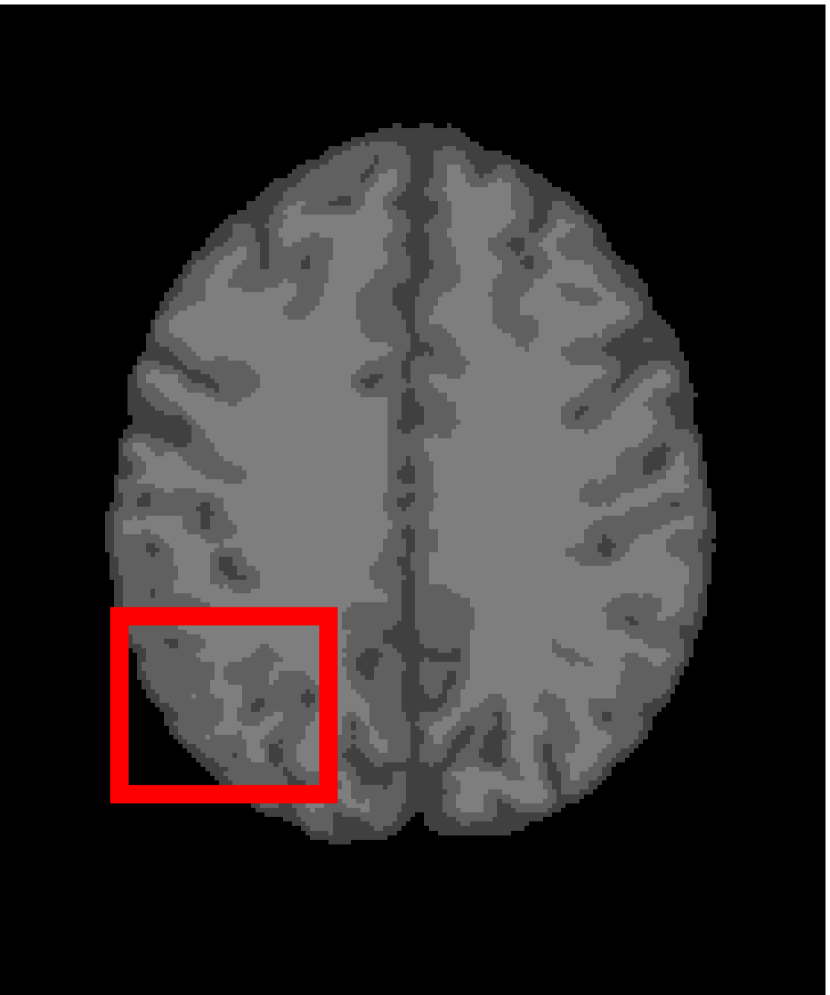

In the second experiments, we segment two medical images coming from a simulated brain database (BrianWeb): http://www.bic.mni.mcgill.ca/brainweb/. The two images are generated by T1 modality with slice thickness of 1mm resolution, 9% noise and 20% intensity non-uniformity. Here, the two images are represented two slices in the axial plane with the sequence of 100 and 110. Moreover, there are golden standard segmentations in the dataset. We set the numbers of clusters to 4. The visual comparisons are illustrated in Figs. 6 and 7.

Figure 6: Segmentation results for the first medical image. From (a) to (l): ground truth, noisy image and results of FCM_S1, FCM_S2, FGFCM, FLICM, KWFLICM, ARKFCM, FRFCM, WFCM, DSFCM_N, and LRFCM.

Refer to caption

Figure 7: Segmentation results for the second medical image. From (a) to (l): ground truth, noisy image and results of FCM_S1, FCM_S2, FGFCM, FLICM, KWFLICM, ARKFCM, FRFCM, WFCM, DSFCM_N, and LRFCM.

By focusing on the marked red square in Figs. 6 and 7, we easily find that FCM_S1, FCM_S2, FGFCM and ARKFCM are sensitive to noise. FLICM and KWFLICM are vulnerable to severe intensity inhomogeneity. FRFCM brings overly smooth results due to the use of gray level histograms. WFCM and DSFCM_N cause several contours to change. However, LRFCM acquires clear contours and suppresses noise adequately. Moreover, we find that the segmentation result of LRFCM is closer to ground truth.